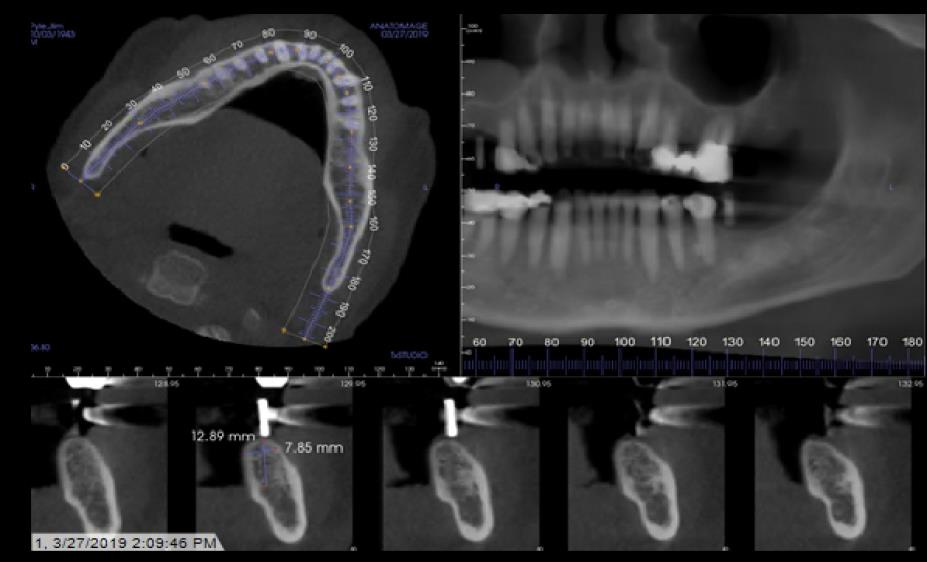

Implant Planning and Restoration #3 and #19

Site #3 Restoration Sequence

Site #19 Restoration Sequence